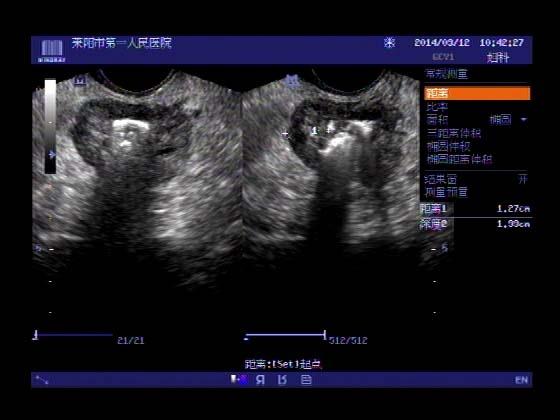

超声入门贴353-----直肠癌伴肝转移

女,66岁